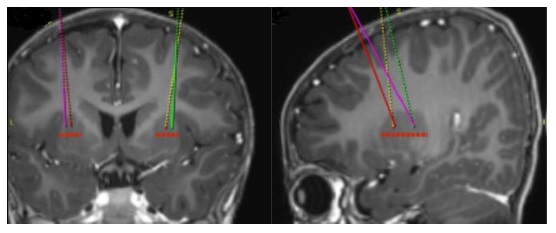

- Using standard neurosurgical stereotactic procedure, brain imaging for stereotactic planning and intraoperative navigation should be done prior to the procedure (see Figure 1).

Figure 1: Four Target Points within the Putamen for Infusion Sites

- After stereotactic registration is complete, mark the entry point on the skull. Surgical access through the skull bone and dura should be performed.